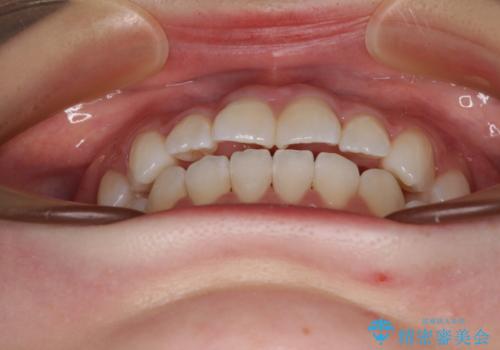

- 前歯のデコボコと非接触の上下前歯を気にして来院された患者様です。

上下前歯の隙間は舌の突出癖によるもので、隙間改善のためには舌のトレーニングがとても重要となります。

口元の突出感はないため、抜歯矯正の適用ではありませんが、デコボコを解消する際に外側に拡大されてしまうと治療前と比べて出っ歯になった印象にもなるため、舌の突出癖の改善が必須となります。

インビザラインによる治療は自己管理が煩わしいとのことで、ワイヤー装置による矯正治療を行うこととしました。